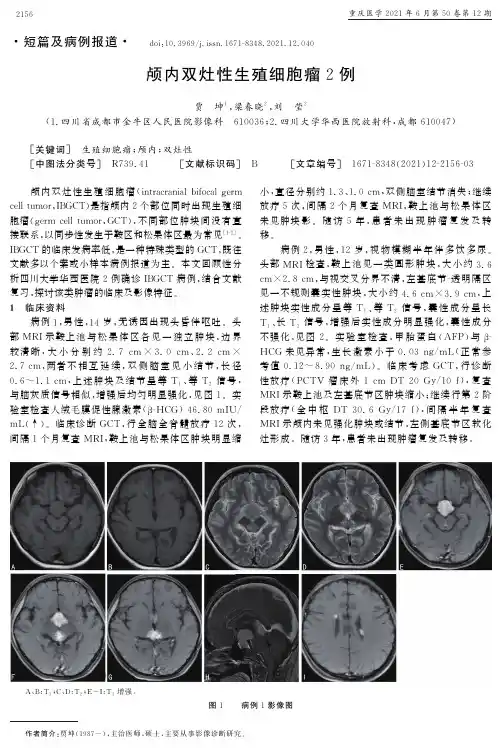

- 大小:5.38 MB

徐冬;徐晓非

【年(卷),期】1997(014)006